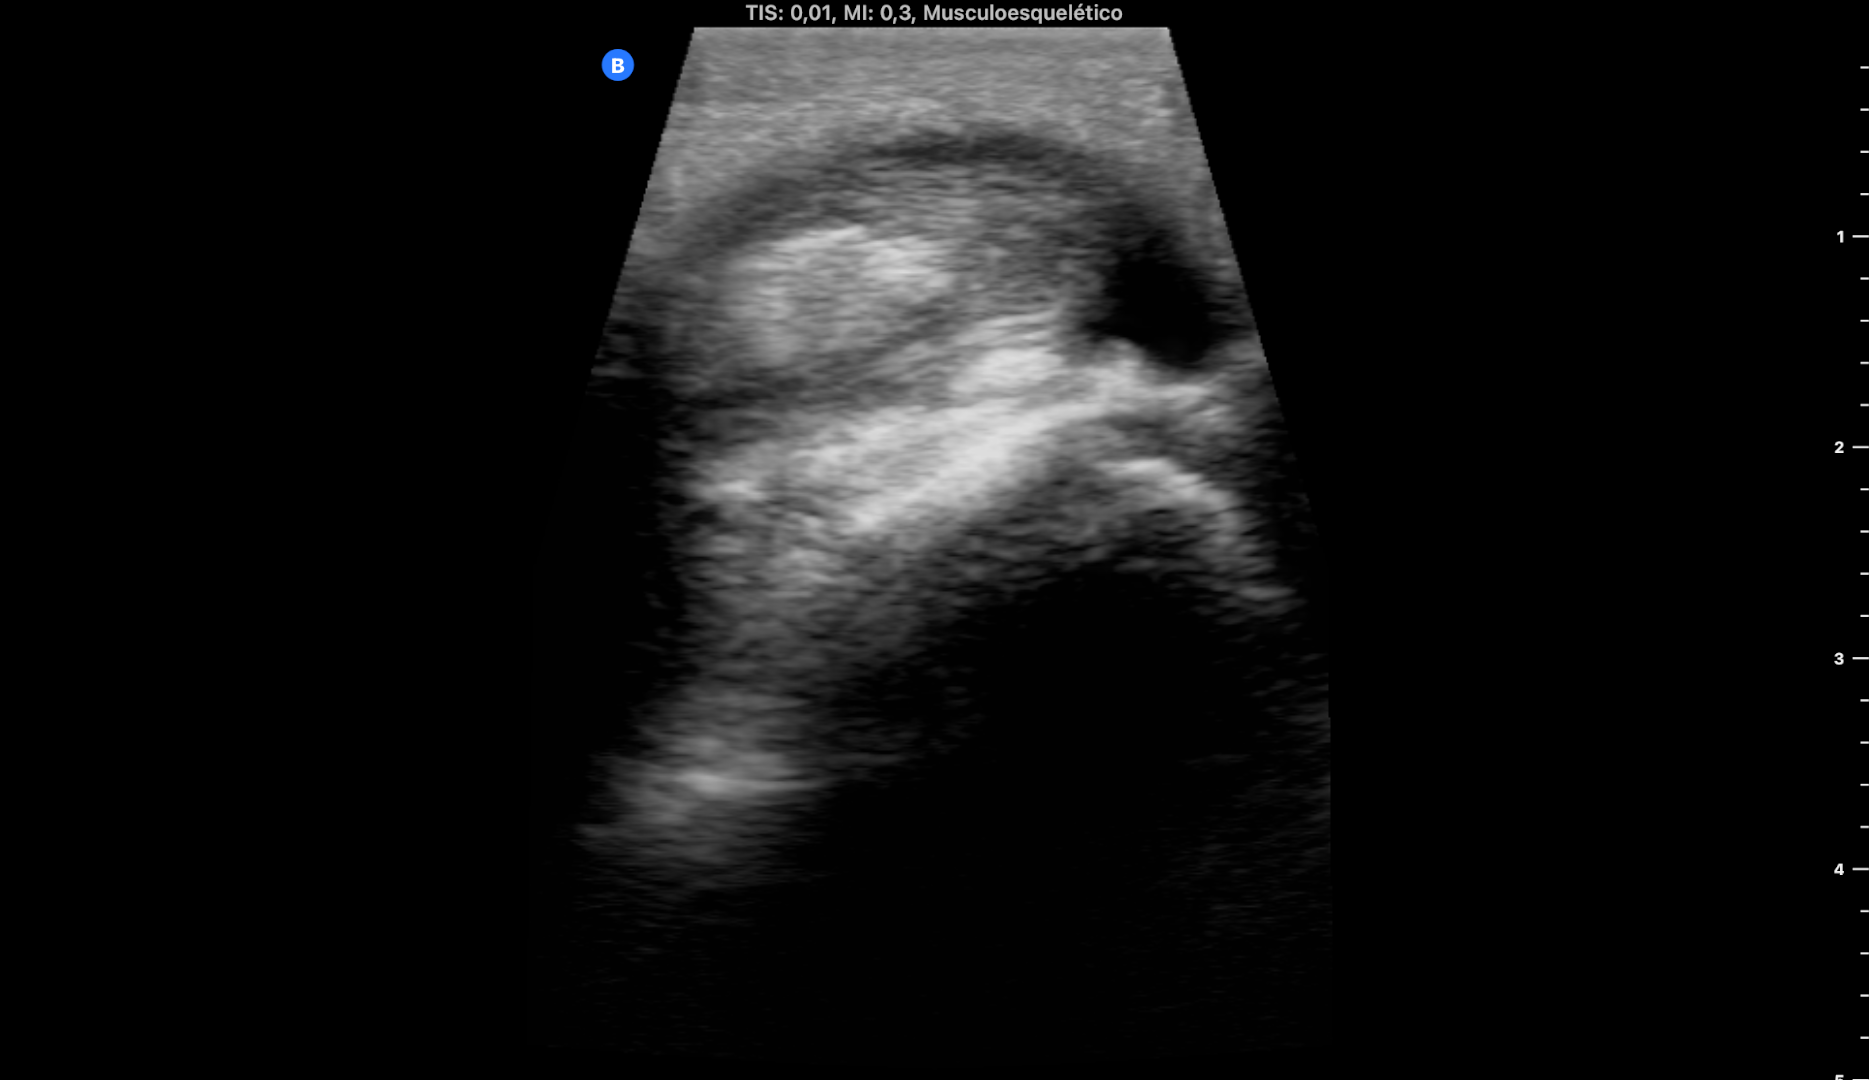

EcoAP: importantes dilataciones varicosas superficiales sin TVP en todo el recorrido de la pierna desde rodilla hacia tobillo. No TVP. No roturas fibrilares. Aquile íntegro.

A nivel del paquete de los tendones peroneos se objetiva importante tenosinovitis y desflecamiento del peroneo largo haciendo una imagen en boomerang.

Le pedí una ecografía reglada a fin de afinar el diagnóstico que confirmó mis hallazgos.

Impresión diagnóstica: tenosinovitis de la vaina del paquete tendinoso de los tendones peroneos a nivel de su paso retromaleolar.